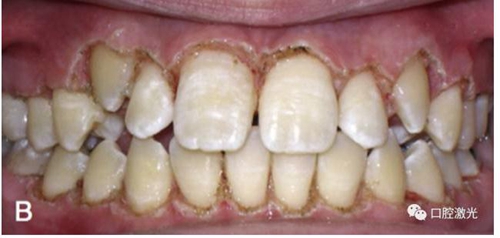

改善口腔衛(wèi)生狀況

有時,會遇到一些口腔衛(wèi)生問題比較嚴重的患者,從而導致牙齦發(fā)炎而腫大。通過改善口腔衛(wèi)生環(huán)境,炎癥可以得到緩解,但增生的牙齦不一定都可以完全恢復。下圖的患者就存在口腔牙齦肥厚問題,同時左上部犬牙存在部分萌出的問題,右上部犬牙存在未萌出問題,這些問題都妨礙了托槽的粘接。因此,實施了全口腔的牙齦整形手術(shù)。去除了多余的牙齦組織,增加了犬牙的暴露面積,從而使托槽的粘接更為便利,同時也提升了患者保持口腔衛(wèi)生的狀況。

激光牙齦整形后即刻

激光治療當天粘接托槽

6周后效果